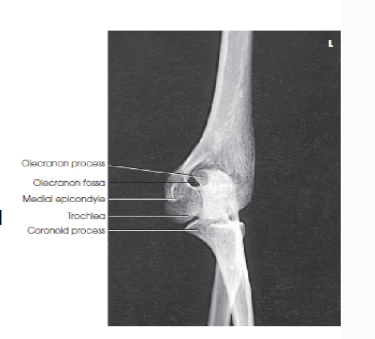

Structures shown/evaluation criteria for AP elbow

• think ulna

-joint space

-epicondyles

-fossae

A

radial head, neck, and tuberosity slightly superimposed over the proximal ulna

elbow joint open and centered to CR

no rotation of humeral epicondyles

coronoid and olecranon fossae approximately equidistant to epicondyles

what should be in profile for a lateral elbow image?

the olecranon process

Eval/structures: what happens to the olecranon process in an AP oblique elbow medial rotation?

the olecranon process appears within the olecranon fossa